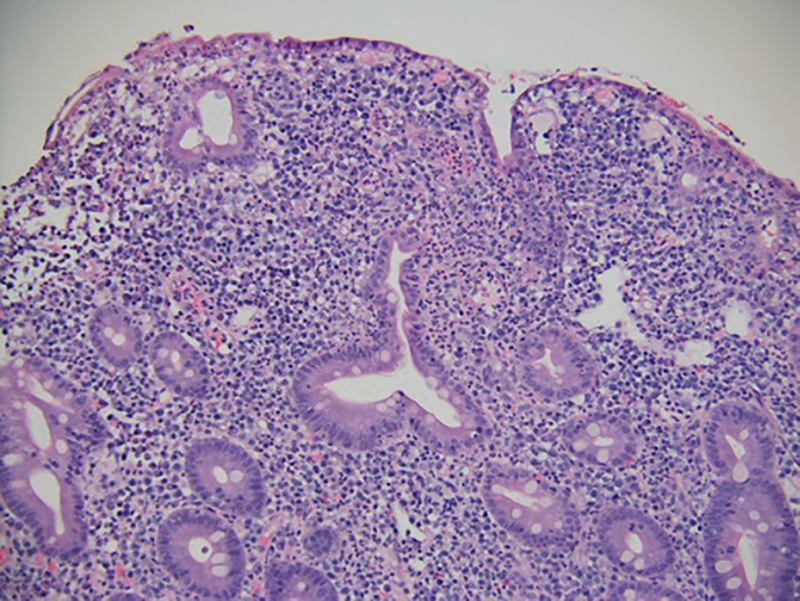

The patient underwent GI tract esophagogastroduodenoscopy 24 hours after admission. Results revealed severely inflamed, diffusely erythematous mucosa in the stomach (Figure 1A) and diffusely erythematous, congested mucosa with overlying exudate in the duodenum (Figure 1B). Gastric biopsy specimens demonstrated focally active gastritis without granuloma formation (Figure 2). Giemsa stain results were negative for Helicobacter pylori. Duodenal biopsy specimens showed active duodenitis with acute cryptitis, crypt abscess formation, and mild villous blunting without granulomas or viral inclusions (Figure 3). Results of colonoscopy with examination of the terminal ileum revealed mild colonic inflammation, extending from the rectum to the mid-ascending colon (Figure 4A). The most severe condition appeared to be in a rectosigmoid distribution. The proximal ascending colon and cecum appeared to be spared. The ileal mucosa appeared erythematous and edematous, with overlying exudate (Figure 4B). Biopsy specimens of the rectum, the sigmoid, and descending, transverse, and proximal ascending colon demonstrated mild active colitis with acute cryptitis, crypt abscesses, and neutrophils within the lamina propria (Figure 5). Biopsy specimens of the distal ileum showed moderate active ileitis with acute cryptitis, crypt abscesses, and focal architectural distortion (Figure 6).

Biopsy specimens of the rectum, sigmoid, and descending, transverse, and proximal ascending colon taken 2 weeks after ipilimumab administration showed active colitis with acute cryptitis, crypt abscesses, and neutrophils within the lamina propria (hematoxylin-eosin, original magnification ×100).

Biopsy specimen of the distal ileum taken 2 weeks after ipilimumab administration showed active ileitis with acute cryptitis, crypt abscesses, and focal architectural distortion (hematoxylin-eosin, original magnification ×100).